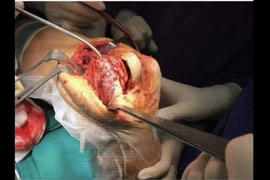

(khoahocdoisong.vn) - Chỉ nghĩ con bị đau xương tuổi dậy thì nào ngờ trẻ 12 tuổi bị u máu khổng lồ phá hủy nửa cánh xương chậu và đe dọa tính mạng. Nhờ kỹ thuật nút mạch và ghép xương, các bác sĩ tại hai bệnh viện kết hợp đã loại bỏ thành công khối u máu và trám xương thành công cho trẻ.